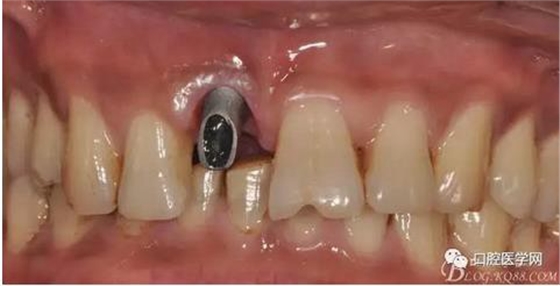

圖7 術(shù)后植入愈合基

圖8 術(shù)后即刻臨時(shí)冠修復(fù)

圖9 三個(gè)月后袖口形成正位照